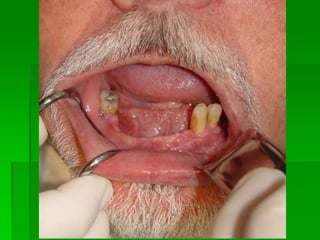

Mandíbula Parcialmente EdentadaQualidade do ossoPosição do feixe neurovascularComprimento dos implantesTamanho do espaço edentadoTipo de carga oclusal

Avaliação da Altura e Largura óssea